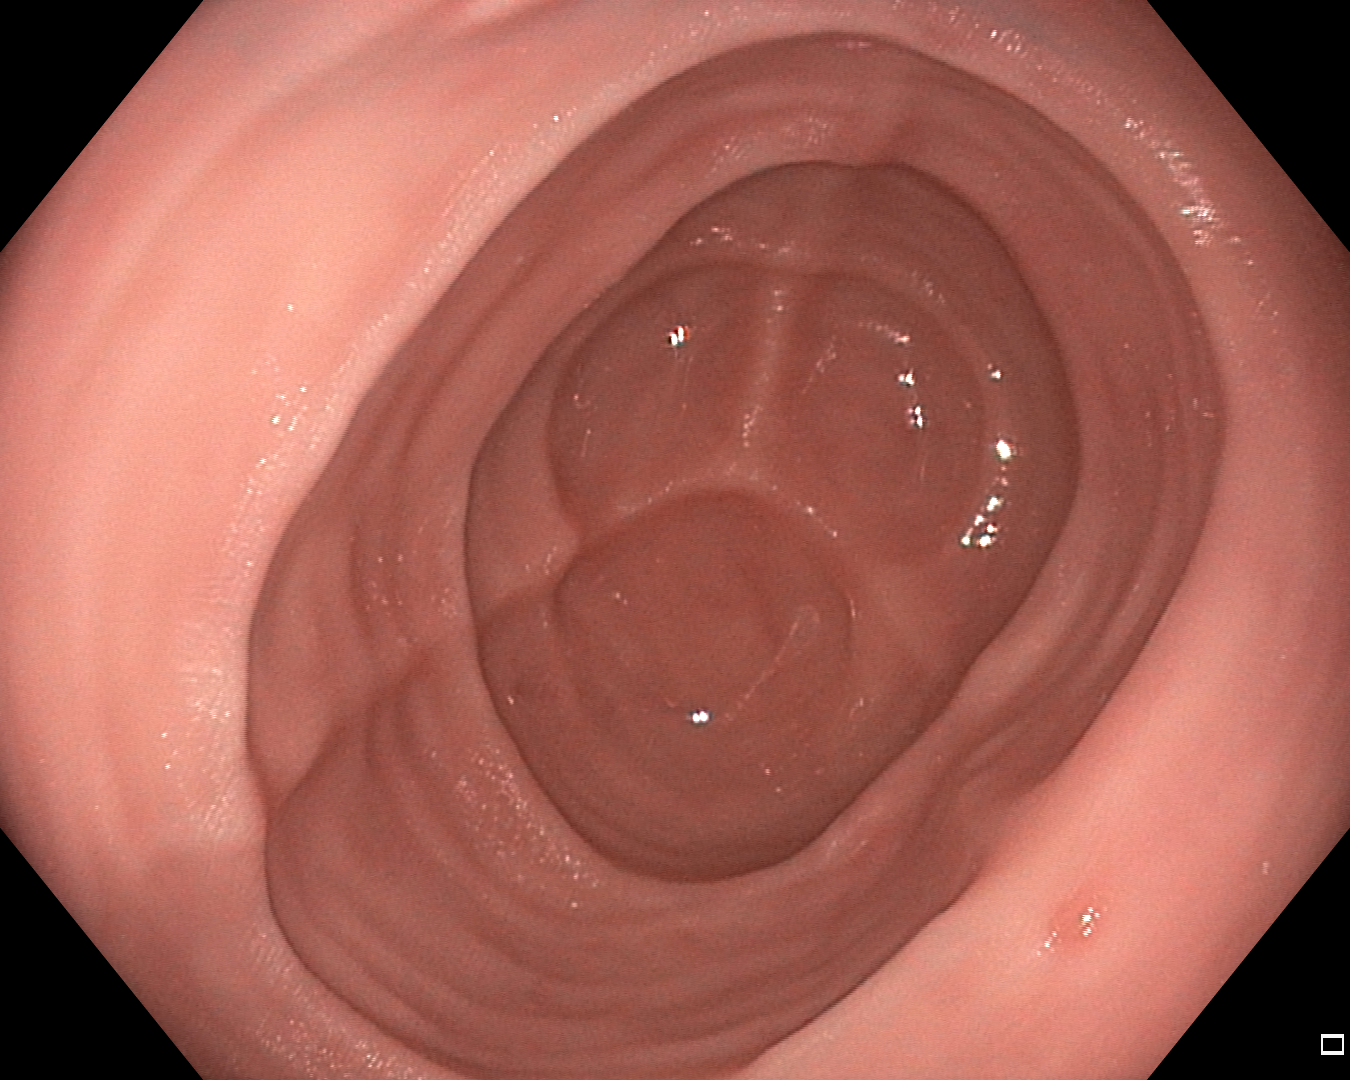

Input Target RN-HK-MC RN-HK-BT RN-IN-MC RN-IN-BT RN-IN-SL RN-NA-NA Refer to caption Refer to caption Refer to caption Refer to caption Refer to caption Refer to caption Refer to caption Refer to caption Refer to caption Refer to caption Refer to caption Refer to caption Refer to caption Refer to caption Refer to caption Refer to caption Input Target VT-HK-MC VT-HK-MA VT-IN-MC VT-IN-MA VT-IN-SL VT-NA-NA Refer to caption Refer to caption Refer to caption Refer to caption Refer to caption Refer to caption Refer to caption Refer to caption Refer to caption Refer to caption Refer to caption Refer to caption Refer to caption Refer to caption Refer to caption Refer to caption

Figure 2: Targets and predictions for two randomly selected instances of the Kvasir-SEG test set. For conciseness, we denote ResNet50s with RN, ViT-Bs with VT, Hyperkvasir-unlabelled with HK, ImageNet-1k with IN, MoCo v3 with MC, Barlow Twins with BT, MAE with MA, supervised pretraining with SL, and no pretraining with NA-NA.